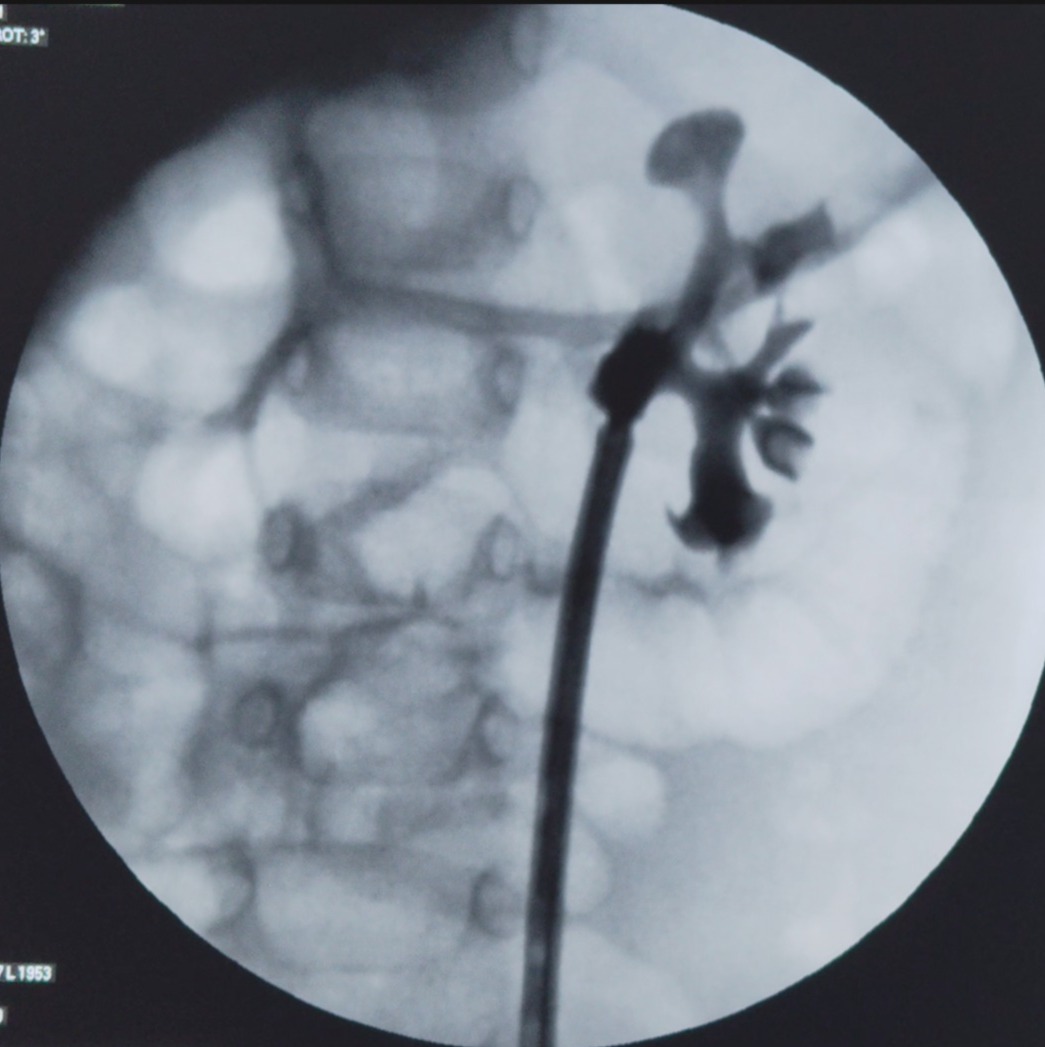

We had a 1-year and 10-day-old baby with bilateral renal stones. We attempted RIRS, though the access sheath could be inserted upto mid ureter , the outflow was not there . RGP showed a large stone burden. Supine PCNL was performed through the middle calyx, and all stones were

We had a 1-year and 10-day-old baby with bilateral renal stones.

We attempted RIRS, though  the access sheath could be inserted upto mid ureter , the outflow was not there .

RGP showed a large stone burden. Supine PCNL was performed through the middle calyx, and all stones were